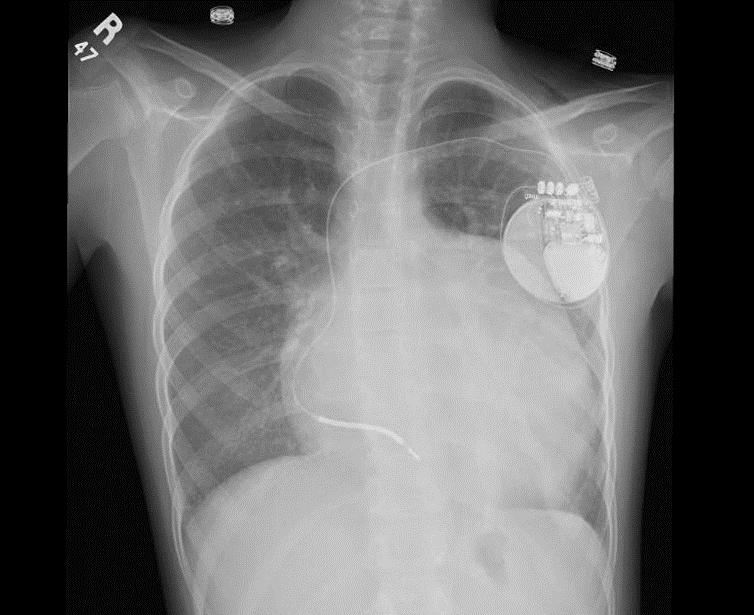

The population of children and young adults requiring a cardiac pacing device has been consistently increasing. The knowledge of indications, pacing leads and devices, anatomical variations and the technical skills required are different than that required in the adult population

The reasons for using ICD have expanded in adults and children population, including in chronic heart failure.

ICDs are recommended for patients who have survived an episode of cardiac arrest, patients with poor cardiac function with evidence of moderate to severe heart failure, patients with inducible ventricular dysrhythmia in a setting of symptomatic CHD and in patients with genetic cardiomyopathy.

ICDs may also be considered as a bridge to orthotopic heart transplantation in pediatric patients, particularly given the longer times to donor procurement in younger patients.

There is paucity of clinical experience and data regarding ICD implantation for primary prevention of SCD in young patients and therefore recommendations are based on extrapolation of data from adult studies. In adults indication of ICD Class I is in case of LVEF< 35% and NYHA 2 or 3, in children we have to balance de risk of the procedure and benefits, and currently as second prevention is just worlwide accepted. Miniturization of ICD devices and ICD subcutaneous will change surely the indications in next years.